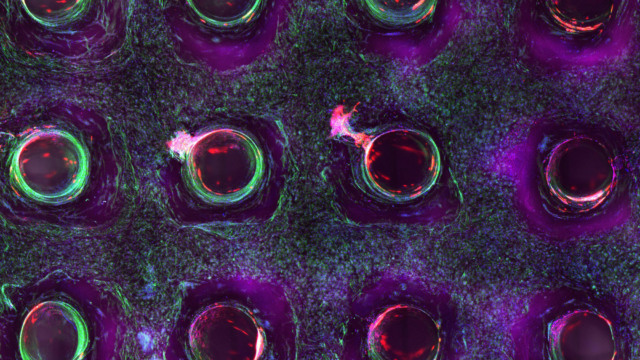

Scientists have successfully bioprinted functional human “mini-livers” and the future is fucking wild!

Man, oh man. Ain’t the future bonkers? Scientists have successfully printed some motherfucking human mini-livers. And, they are capable of all performing all the functions of human livers. Such as? You know, “building proteins, storing vitamins and secreting bile” and shit. Amazing. Admittedly, there is still far, far to go from these organoids being actual livers. But, it’s a rad as fuck step.